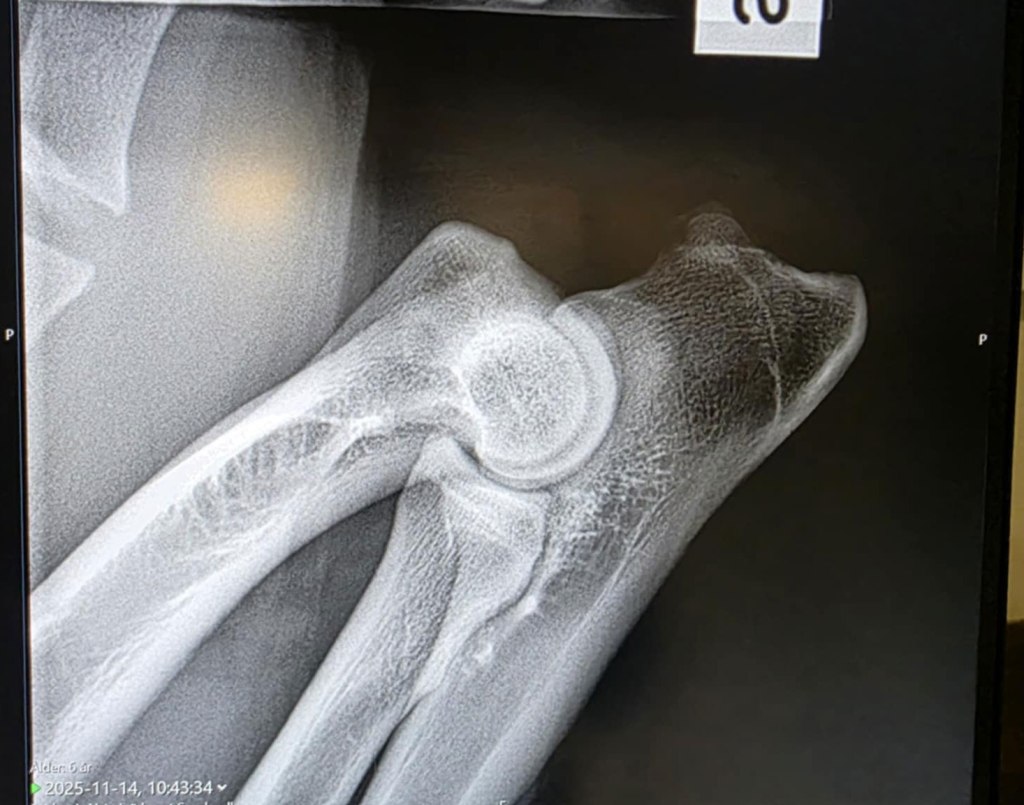

När vi röntgade hans ED hade vi i ärligheten lite ångest utifrån hans historia med sitt bakben där han var skadad i princip i två år om man räknar in hans långa rehabiliteringsperiod. Skulle inte vara konstigt att man ev hittade exempelvis någon form av artos, han är ju dessutom något till åren kommen när röntgen genomfördes. Men när vi såg bilderna på Veterinärhuset i Sundsvall så kunde till och med två riktiga amatörer som jag och Kenth se att de förmodligen

var utan anmärkning och det var också det svar vi senare fick efter avläsningen hos SKK.